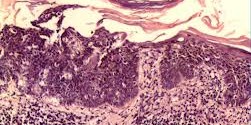

La Fiebre maligna verrucosa es una enfermedad infecciosa rara caracterizada por anemia (disminución de los hematíes o glóbulos rojos circulantes), fiebre anormalmente alta y erupciones crónicas de la piel que se pueden acompañar de dolor. La Bartonella bacilliformis es un parásito bacteriano intracelular facultativo de los eritrocitos humanos y de las células endoteliales. Las infecciones por B. bacilliformis son un …

El Botón de los andes es una enfermedad infecciosa rara caracterizada por anemia (disminución de los hematíes o glóbulos rojos circulantes), fiebre anormalmente alta y erupciones crónicas de la piel que se pueden acompañar de dolor. La Bartonella bacilliformis es un parásito bacteriano intracelular facultativo de los eritrocitos humanos y de las células endoteliales. Las infecciones por B. bacilliformis son …